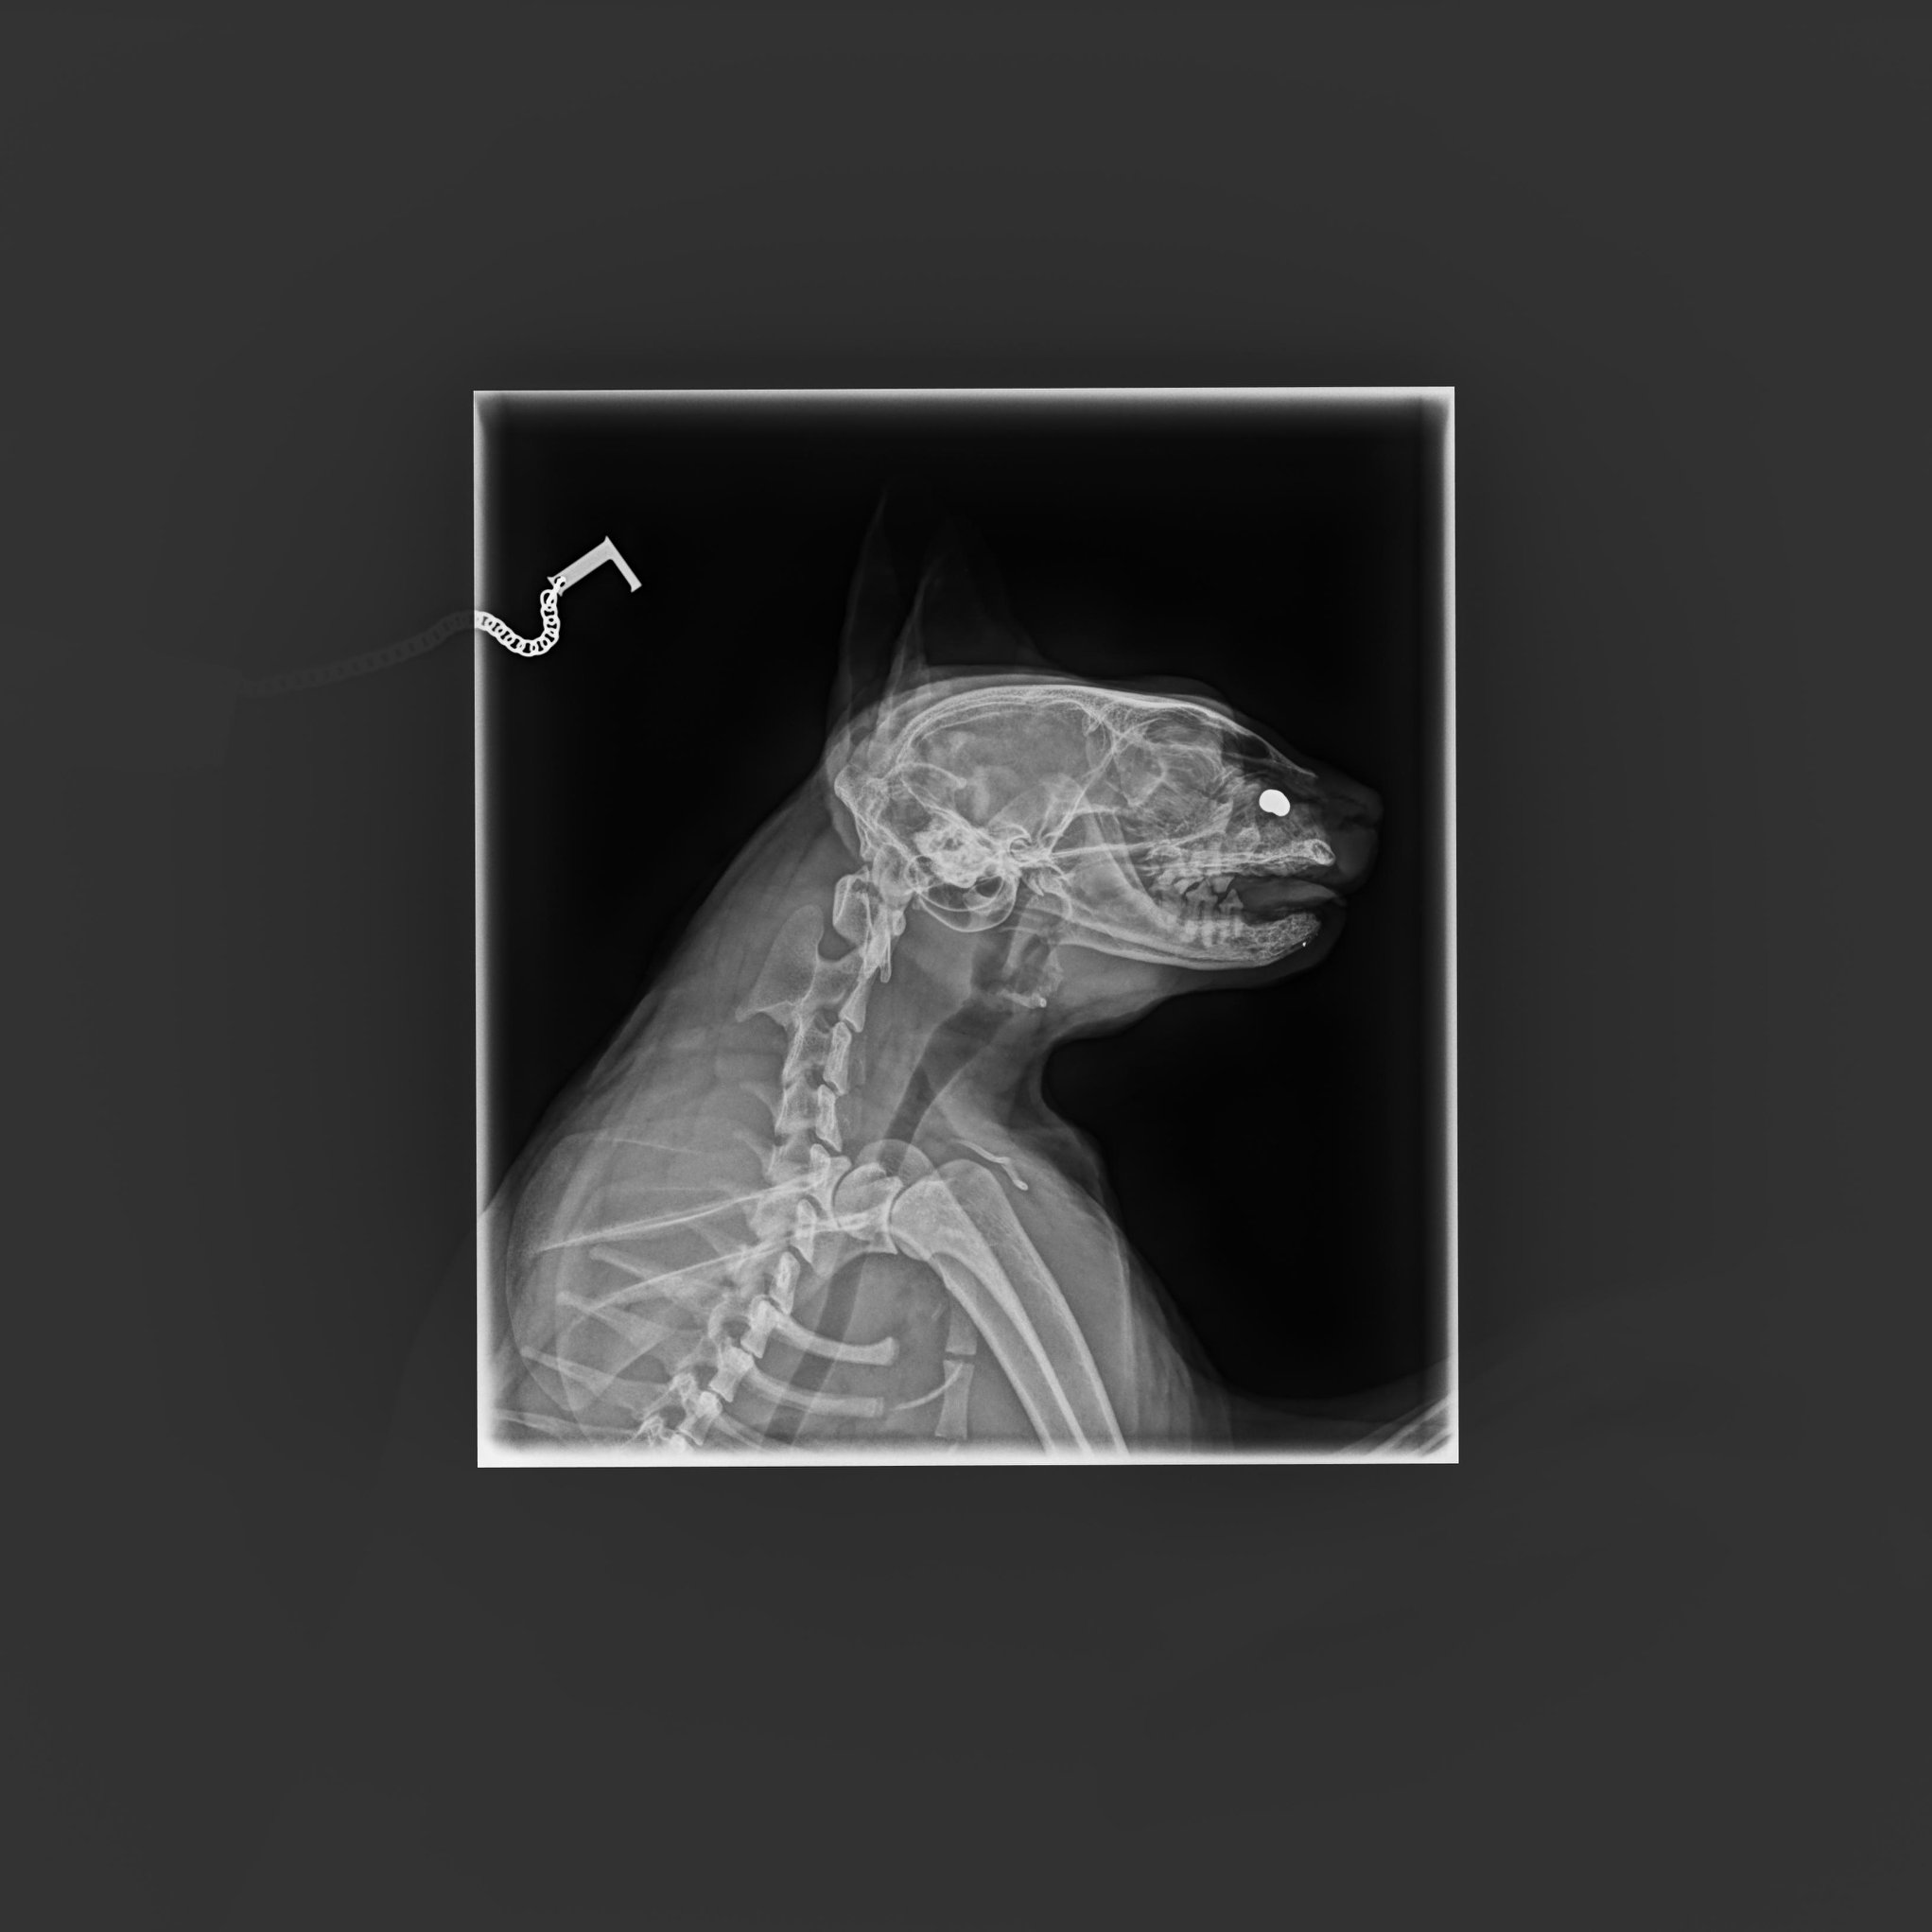

🔶Poslední týdny se rýma Šmudlovi zhoršila a tak se přistoupilo k vyšetření, k rhinoskopii. Ukázalo se, že příčinou je diabolka, která způsobuje Šmudlovi velké obtíže. Bohužel je však umístěna za kostí, ta se díky olovu rozpadá, ale diabolku nelze nijak vyndat. Diabolek má Šmudla v tělíčku i s touto osm. Kvůli tomu musí chudák Šmudla trpět..